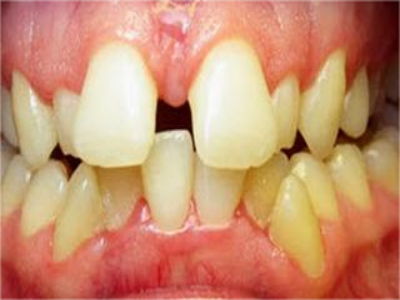

阻生牙是指由于邻牙、骨或软组织的阻碍而只能部分萌出或完全不能萌出,且以后也不能萌出的牙。引起牙阻生的成因,主要是由于颌骨缺乏足够的空间容纳全部恒牙。常见的阻生牙为下颌第三磨牙、上颌第三磨牙及上颌尖牙。

阻生牙可反复引起冠周炎,或引起邻牙牙根吸收和破坏,位置不正,不能完全萌出,好发部位是上、下颌第三磨牙。

阻生牙主要原因是随着人类的进化,颌骨的退化与牙量的退化不一致,导致骨量相对小于牙量,颌骨缺乏足够的空间容纳全部恒牙。